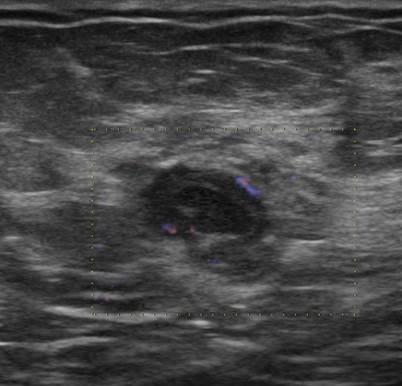

Ung thư vú

» Thông tin: Nữ giới – 50 tuổi.

» Lâm sàng: Kiểm tra sức khỏe.